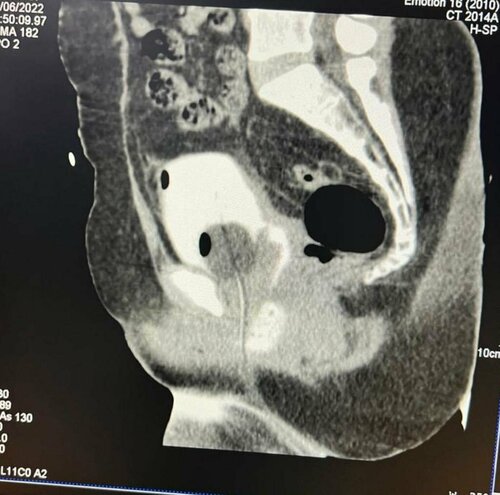

A 72-year-old man was suffering from abdomen pain and it was making life difficult. He visited Urozoone Holistic Kidney Care Clinic and got consulted ...